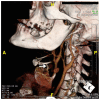

We present the case of a mixed martial arts (MMA) cage fighter who presented to the emergency department with a right sided common carotid artery pseudoaneurysm as a result of a neck trauma at an MMA event. We discuss the management of blunt force neck trauma, differential diagnosis, imaging findings and review the literature on blunt cerebrovascular injury following blunt force injury to the neck.